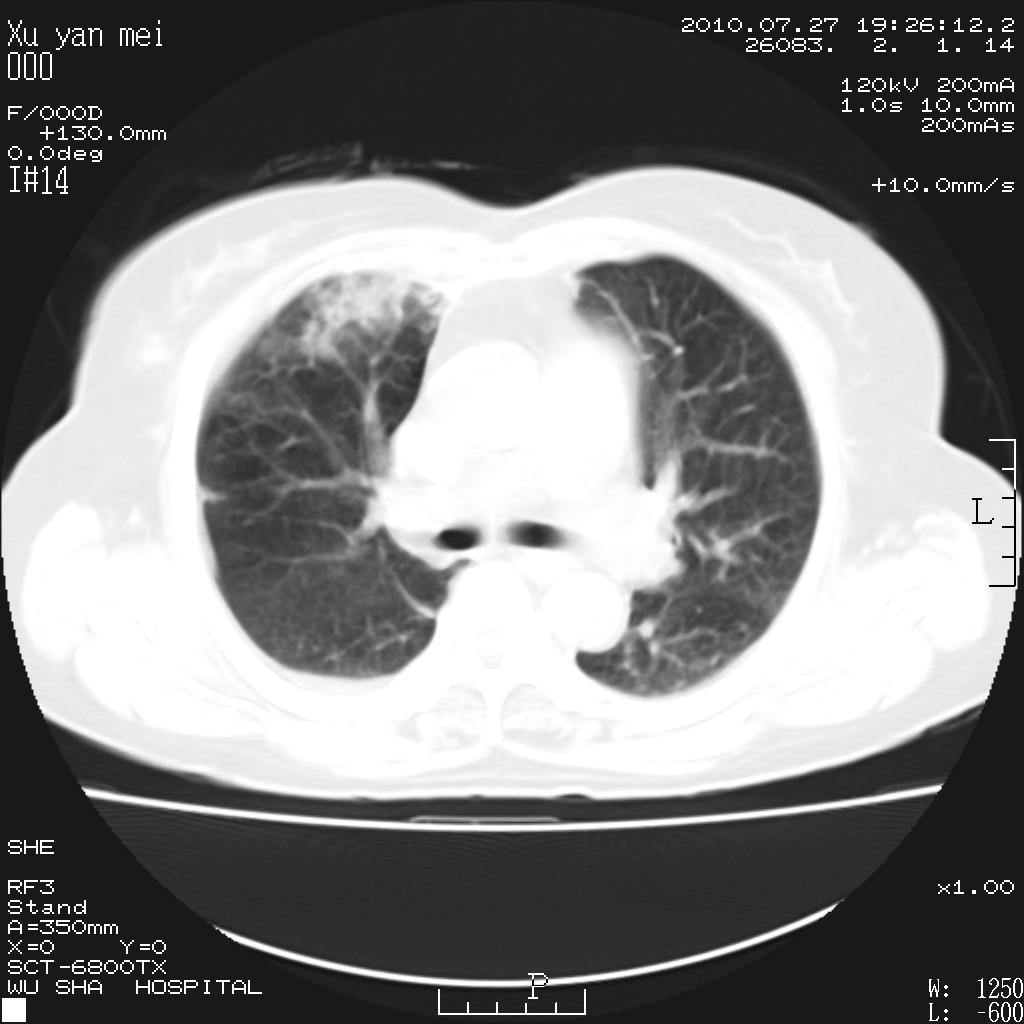

女,60岁,胸痛就诊,右肺结核?炎症?其它?(胸片右侧中上肺野确实看不到什么啊)

1)考虑两肺感染性病变;建议抗炎治疗后复查。2)双侧少量胸腔积液。

1)考虑两肺感染性病变;建议抗炎治疗后复查。2)右侧少量胸腔积液。

双肺炎症可能性大,建议抗炎后复查。右侧胸腔少量积液。双侧胸膜轻度增厚。

考虑两肺感染性病变;不除外肺栓;建议抗炎治疗后复查。